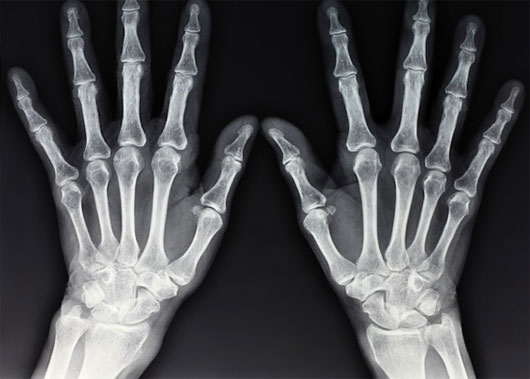

Loại tia X-quang mới có thể đưa ra những hình ảnh cụ thể của đối tượng quan sát. (Ảnh: ShutterStock)

Khi chụp X-quang một vật thể nào đó bằng cách là truyền, hấp thụ hoặc phân tán tia X, phương pháp cũ hoạt động bằng cách thu thập các tia sáng truyền đi, xoay mẫu và dựng lại hình ảnh 3D của vật thể. Tuy nhiên, với tia X phân tán, chúng ta có thể thu được thông tin về cấu trúc cũng như tính chất hóa học của vật thể, dù nó ở dạng tinh thể pha lê với kích thước nano.

Nhờ tia X này, chúng ta có thể hiểu rõ thuộc tính của vật liệu để xem xét phản ứng hóa học tại chỗ, phân biệt các mô khỏe và mô bệnh, xác định khoáng sản và đá chứa dầu hoặc xác định chất cấm, hàng lậu trong hành lý khách hàng.